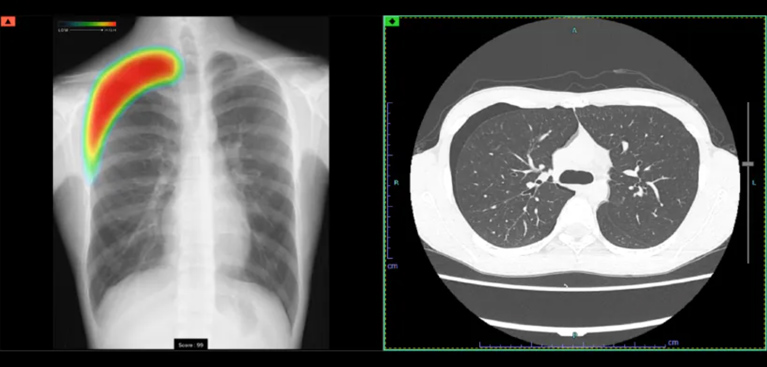

AI診断システムCXR-AID(富士フィルム社)を導入しております。胸部レントゲン画像をAIによって解析し、結節や腫瘤陰影・浸潤影(炎症)・気胸などが疑われる場合、色付けによって表示されます。これにより医師とAIのダブルチェックが可能となり見落としのリスク軽減・初期段階でキャッチできるなどのメリットがあります。

CXR-AIDは、AIが胸部の画像を数十秒で読み取り、気になる可能性のある部分をマークして表示します。医師はAIが示した箇所を確認しながら診断を行うため、見落としが少なく、より正確な診断につながります。AIと医師が一緒にチェックすることで、病気を早めに見つけられる体制を整えています。

検出対象となるのは、主要な肺疾患に関連する画像所見である「結節・腫瘤影」、「浸潤影」、および「気胸」の3つです。

0~100に分けられた確信度スコアの最大値が数値として表示されます。

胸部レントゲン所見のスコア値が低い場合、血管や骨、過去の炎症による瘢痕など、問題がなく治療も必要ない所見の可能性が高くなります。この場合は精密検査の必要はありません。